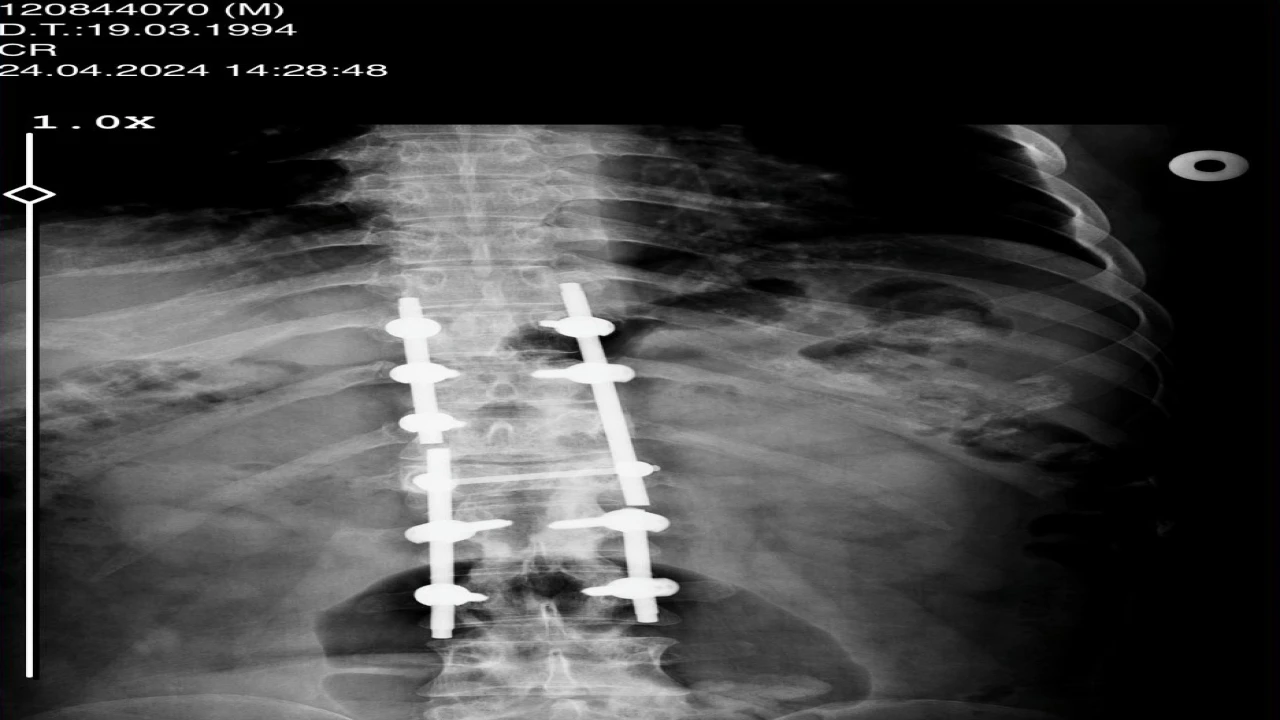

Konya’daki Afşar ve Bağbaşı Barajı arasındaki Mavi Tünel’in inşaatında Palet İnşaat bünyesinde ekskavatör operatörü olarak çalışan Sezgin Keşto (31), 1 Mart 2019’da, Cezmi Çelik’in (54) kullandığı beton mikserinin kaza yapması sonucu ağır yaralandı. Bu sırada sürücü Cezmi Çelik ise hayatını kaybetti. Araçtan çıkarıldıktan sonra Selçuk Üniversitesi Tıp Fakültesi Hastanesi’ne kaldırılan Keşto’nın omurgasının kırıldığı, omuriliğinin zedelendiği belirlendi. Geçirdiği ameliyatın ardından 3 gün yoğun bakımda kalan Keşto, 6 aylık tedaviden sonra taburcu edildi. Bir daha yürüyemeyeceğini öğrenen Keşto, Adana’daki ailesinin evine döndü.